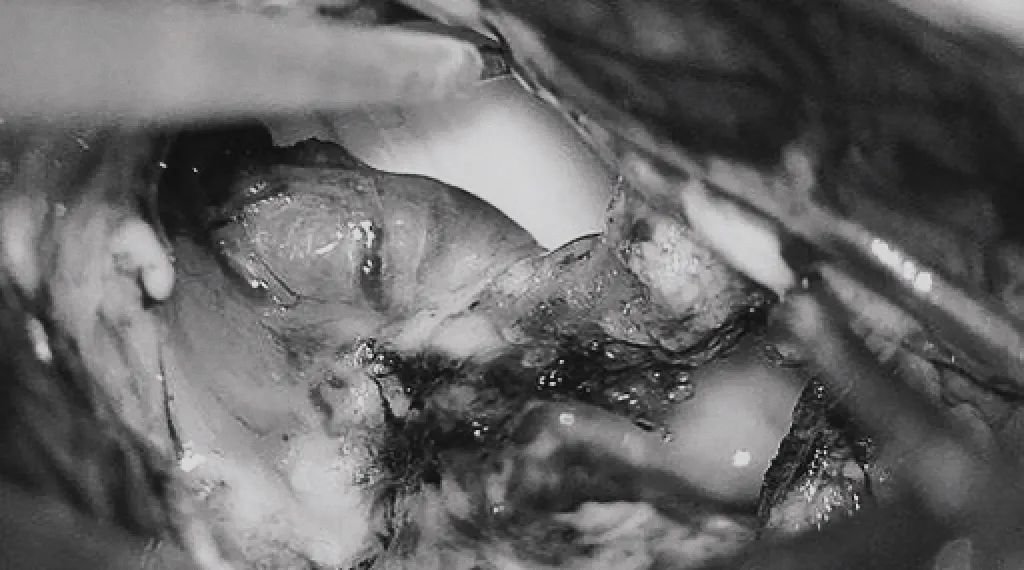

▼移除AVM

▼显露PCA周围至其ParOccA和CalcA(P2P)分叉

▼沿小脑幕见PCA的大脑脚段(P2A)和硬化的供血支。